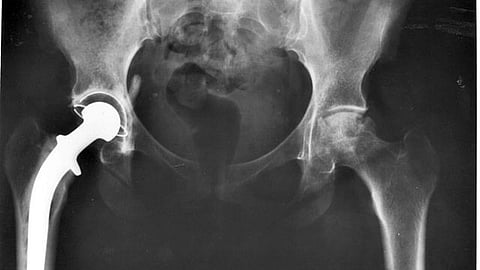

Total hip and knee replacements are challenging enough for patients. When an infection occurs in the aftermath, the results are often disastrous, requiring potent antibiotics and revisionary surgery.

After hip and knee replacement surgeries, pathogenic bacteria can adhere to the surface of the joint prosthesis and form a dangerous biofilm. Gold standard clinical methods use potent antibiotics and further surgery, including removal of infected tissue and transplantation of new tissue, to treat these infections. However, these strategies run into problems with hyper-resistant bacteria caused by the abuse of antibiotics, persistent damage caused by tissue removal, difficulties in obtaining tissue donors, and toxicity and immune system complications.